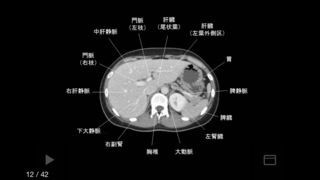

e画像解剖では、体の断面図を詳しく確認出来るCTやMRI関連の医療専用映像図譜集アプリです。このアプリでは、胸、お腹、頭、単純画像の4通りの範囲を1つに纏めています。医学部で授業を受けている高学年ならば、解剖学の知識や医師国家試験に合格する有効手段として上手く活かせます。国家試験の中で出題されやすい写真解剖テストのアプリも準備されています。5ミリのCTやMRIデータを通常での診察治療などに使用出来ます。患者さんが抱えている病状や診断結果の内容を伝える場合などで、必ず役立つ大切なアイテムにもなります。

医師や医学生にとって解剖学は基本中の基本であり、知っておかなければ治療を行うことはできません。「e画像解剖」は医師や医学生向けのCT画像やMRI画像を豊富にそろえている医療画像集になります。フレーム部分は無料となっており、画像は必要なものを個別に購入する必要があります。しかし、数千円から数万円もする医学書を購入することを考えれば、必要な画像を個別購入できるこのアプリはお徳と言えるでしょう。自分の専門分野で使う頻度が高い画像をダウンロードしておけば、いつでもスマホやタブレットで参照することが出来ます。画像だけでなく、医学生に向けた解剖学クイズも発売されており、国家試験対策などにいかすことが出来ます。